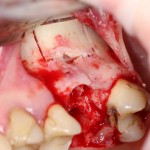

На фотографии ниже нам повезло — вы заметили перфорацию в ходе подготовки лунки под имплантат и приняли меры по ее устранению:

Однако, так везет далеко не всегда. Именно поэтому метод закрытого синуслифтинга имеет ряд ограничений: